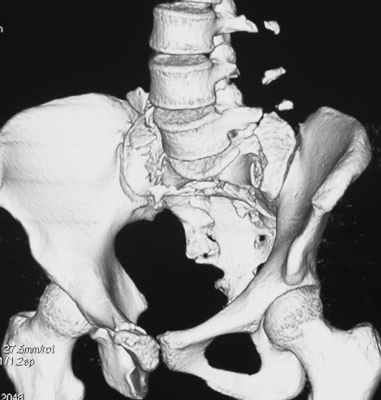

Травма 21.августа 2005г. На девочку в лесу упала береза. Доставлена в ближайшую ЦРБ. При поступлении установлен диагноз: Травматический шок 2-3 ст. Тупая травма живота. Забрюшинная гематома. Перелом костей таза с нарушением целостности тазового кольца. Перелом лонной и седалищной костей справа. Перелом поперечных отростков L3 - L5. Разрыв КПС справа. При поступлении выполнена диагностическая лапароскопия — выявлена обширная забрюшинная гематома. Было наложено скелетное вытяжение за бугристости обеих б/берцовых костей, больная уложена в гамак. Через неделю скелетное вытяжение демонтировано, гамак снят. Девочка уложена в положение «лягушки». Контрольные рентгенограммы через 4 недели после травмы. Заподозрен перелом дужки L5. Больная 26 сентября 2005 г. переведена в областную больницу в отделение детской ортопедии. При поступлении в локальном статусе: пальпация и перкуссия остистых и поперечных отростков L4-5 болезненная. Пальпация костей таза б/болезненная. С-м натяжения слабо положителен. Осевая нагрузка положительная. Движения в т/б суставах ограничены, болезненны. C-м прилипшей пятки отрицательный. C-м Ларрея и Варнейля отрицательный. Периферическая гемодинамика не нарушена.Неврологический статус: вторичная двусторонняя радикулопатия L5-S1. 29 сентября произведена компьютерная томография позвоночника и таза.

Судя по томограммам, радикулопатия может быть из-за компресии "конского хвоста" смещенным крестцовым позвонком, это хорошо видно на втором слева снимке. Если этот сегмент будет нестабилен и будет сохраняться неврологическая симптоматика, придется оперировать. Если неврологическая симптоматика уйдет и перелом стабилизируется, то можно обойтись без операции.